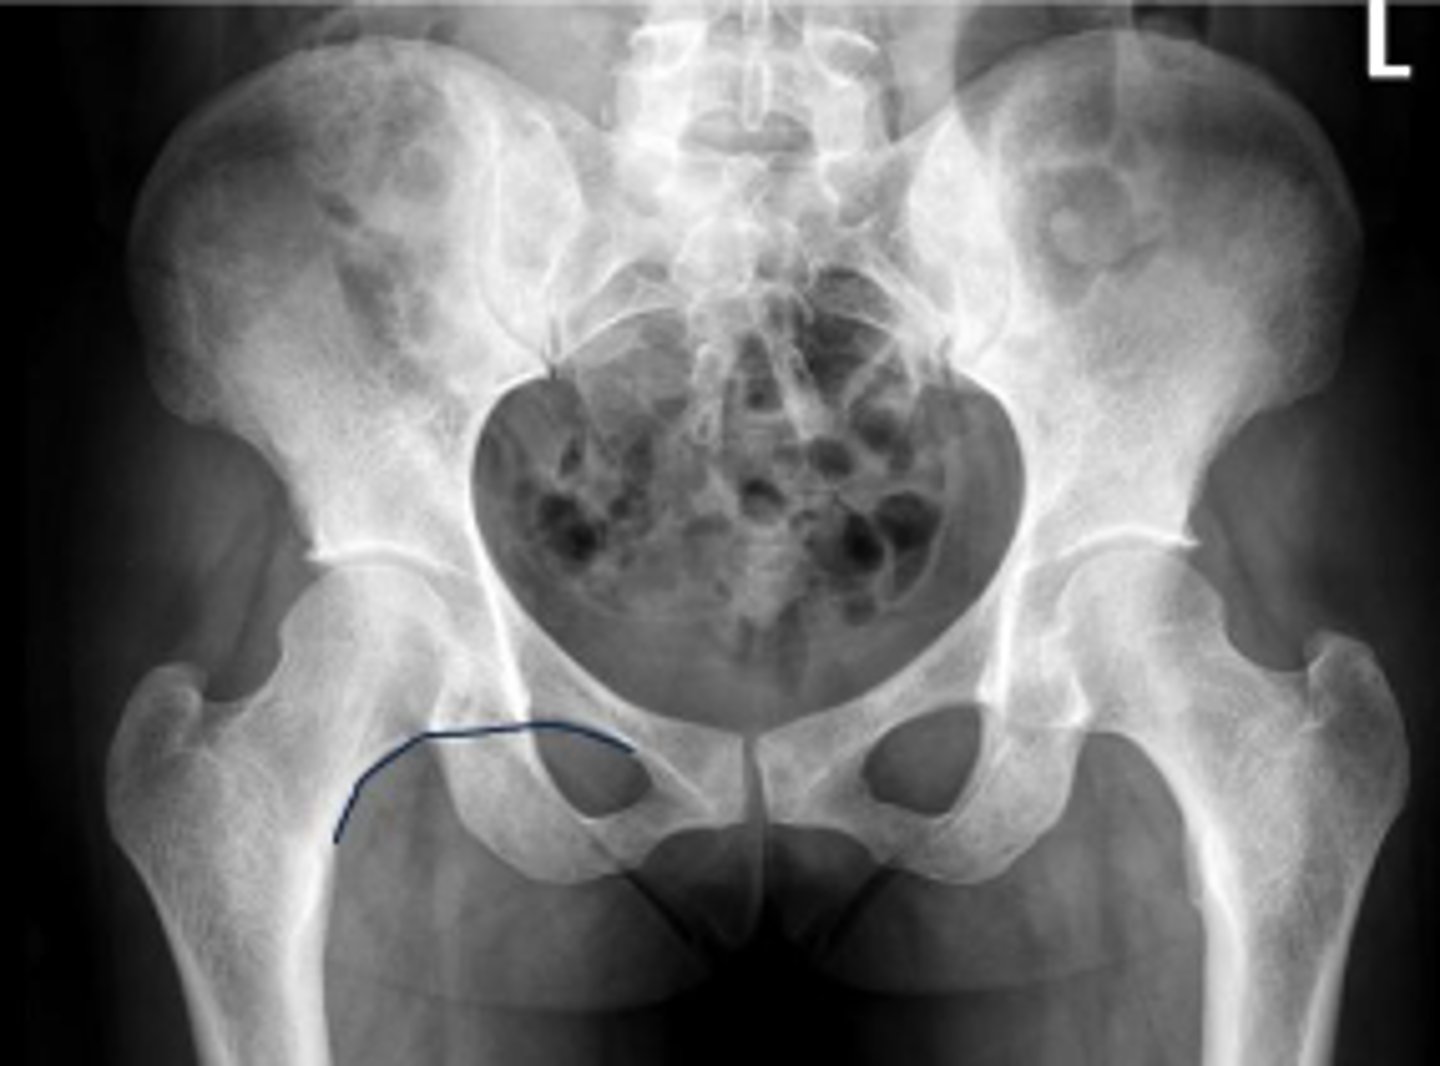

AP pelvis or bilateral hips

What is the name of the radiographic view?

Bilateral frog leg view

Phleboliths

What are the arrows pointing to?

Right ischial spine

Posterior rim of the right acetabulum

Anterior rim of the right acetabulum

Right sacroiliac joint space

What joint space is the arrow pointing to?

Lesser trochanter of the right femur

Greater trochanter of the right femur

Right posterior inferior iliac spine

Intertrochanteric line of the right femur

Right ischial tuberosity